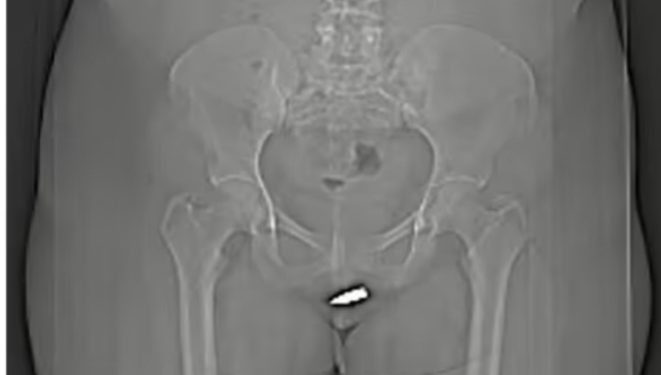

CT scans showed that the bullet had penetrated the clitoris after being fired into her vulva, meaning she needed surgery to have it safely removed.

Doctors said the case is the first of its kind. They can remove the object from the vagina but extra care should be taken not to damage the urethra and pelvic area.